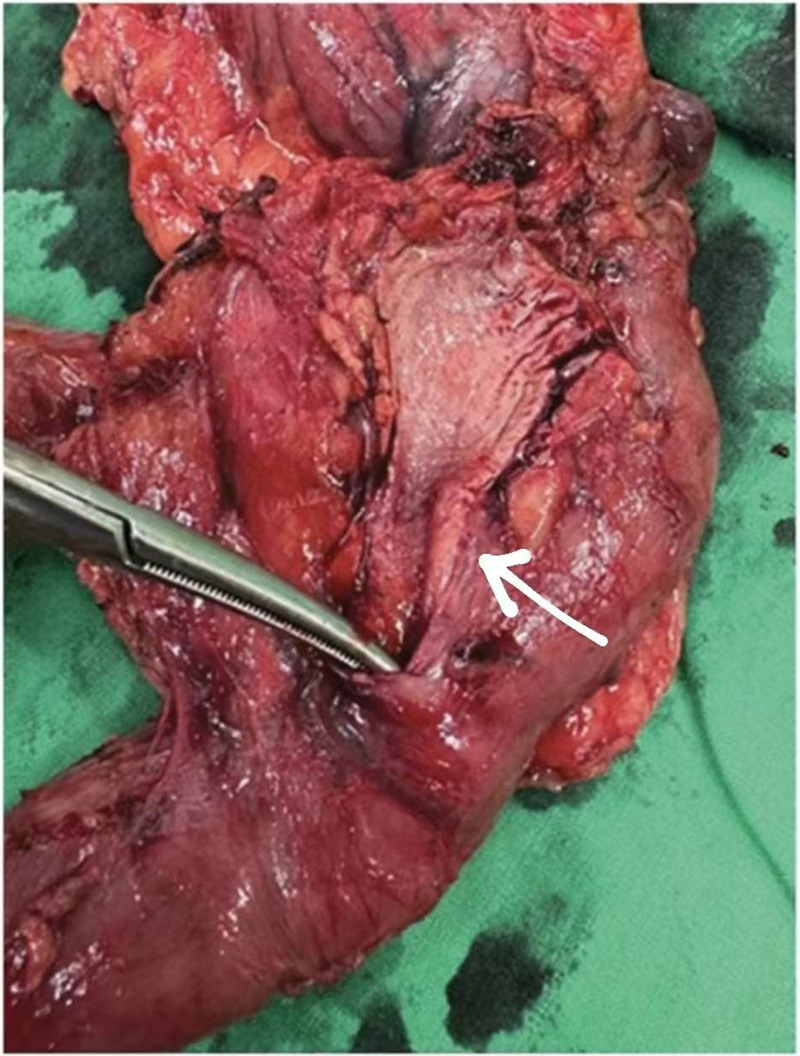

A 54-year-old woman with a medical history of hypertension and hyperlipidemia presented to the outpatient department complaining of persistent epigastric dull pain. Abdominal ultrasonography revealed significant dilation of the CBD (up to 15.2 mm); however, no obvious intraductal mass, bile duct wall thickening, CBD stones, or pancreatic head tumors were identified (Fig. 1). Subsequent abdominal CT demonstrated a contrast-enhanced tumor-like mass measuring approximately 1.6 cm in the distal CBD, characterized by wall thickening without distinct intraductal lesions. Magnetic resonance imaging (MRI) confirmed narrowing of the distal CBD with mild upstream dilatation measuring 10.9 mm, without liver, pancreatic, or lymph node involvement (Fig. 2). Physical examination of the abdomen revealed no tenderness, and the patient denied experiencing fever, nausea, vomiting, or loss of appetite. Laboratory investigations revealed an elevated level of γ-glutamyl transferase (GGT) at 130 U/L, while regular blood tests, as well as levels of carcinoembryonic antigen (CEA), cancer antigen 153 (CA153), and CA199, were within normal ranges (Table 1). Suspecting a bile duct tumor, a Whipple procedure was performed for both diagnostic and definitive treatment purposes (Fig. 3). Histological examination of CBD sections revealed adenomyomatous hyperplasia characterized by clusters of benign biliary glands embedded within fibromuscular stroma and surrounded by lymphoplasmacytic inflammatory cells (Fig. 4). The lesion exhibited no signs of malignancy, confirming its benign nature. The patient experienced a satisfactory recovery and was discharged 19 days post-surgery.

This case presents a unique aspect in which preoperative CT imaging revealed distal CBD dilation and a contrast-enhanced tumor-like mass, a presentation typically indicative of malignancy. However, the final pathology report confirmed a benign diagnosis. This scenario contributes valuable insight into the potential for benign etiologies in cases presenting with similar radiological features, thereby enhancing diagnostic considerations in clinical practice. Preoperatively, abdominal ultrasonography revealed significant dilation of the CBD. However, no obvious findings of intraductal tumors, bile duct wall thickening, CBD stones, or pancreatic head tumors were observed. Suspecting distal bile duct obstruction, an abdominal CT scan was performed, which confirmed the presence of a distal CBD tumor. An MRI was subsequently performed for confirmation. Given the strong suspicion of malignancy based on CT and MRI findings, endoscopic ultrasonography (EUS) was not performed, and the decision was made to proceed directly with surgery. During surgery, the lesion was identified as thickening of the distal CBD wall within the pancreatic head. This anatomical location explains why preoperative abdominal ultrasonography failed to detect the lesion, revealing only dilated bile ducts. If EUS had been performed preoperatively, it might have visualized the stenotic portion of the distal CBD in the pancreatic head, but it cannot reliably distinguish whether the cause is a malignant tumor, or a choledocholithiasis.